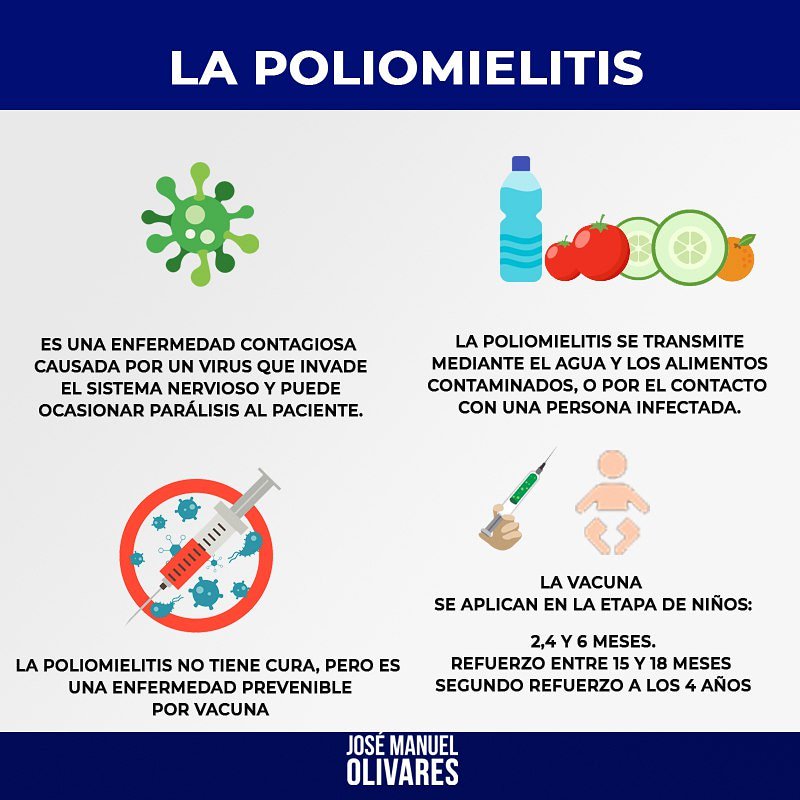

Para una amigo se solicita con urgencia rytmonorm 150mg. Gracias por el apoyo Fundacion Jesed Codevida ESEdeSalud. 🕯️Vzla🕯️ ACONVIDA αηση мυη∂ιαℓ Buscando Medicinas Medicinas Venezuela @buscatumedicina @Farmarato S.O.S DONACIÓNES VENEZUELA